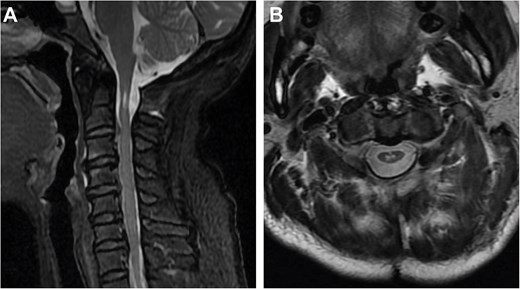

We used a posterior cervical approach to resect the posterior arch of C1. There were no intraoperative complications during the procedure. The patient’s symptoms improved dramatically following the operation. The cervical spinal cord lesion showed no evidence of progression on the 18-month follow-up MRI (Fig. 4A and B). To present, the patient is stable, with no symptoms or signs of recurrence.

Two-year postoperative MRI results. (A) Sagittal T2-weighted MRI. (B) Axial T2-weighted MRI.

CHII lesion is a unique imaging finding defined by Van Dijk et al. in achondroplasia, presenting as hyperintense lesions of the spinal cord on T2-weighted MRI in the absence of local spinal cord compression [4]. According to Khoo et al.’s study, a CHII lesion was found in 47.5% of symptomatic achondroplastic individuals; it appears to be a stable anomaly with no progression or change in morphology [20]. Our case provides evidence for this notion, as the patient’s hyperintense lesions did not change during the 18 months of follow-up after surgery. The finding of CHII lesions in our patient suggests a link between congenital hypoplasia of the atlas and achondroplasia.